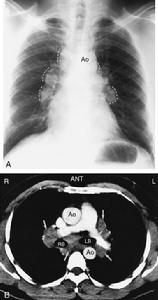

①胸膜斑:雙側胸壁中下部位對稱性三角形陰影內緣清晰偶見單側形態不規則者部分胸膜斑有鈣化(圖1)

對於常規CT掃描在石棉沉著病診斷中的作用尚存在爭論有人認為常規CT掃描在早期發現接觸石棉的人群的胸膜增厚及肺實質纖維化等方面比常規X線胸片有明顯更高的敏感性。高解析度CT(HRCT)的診斷價值可能更大Aberle等對29例有職業性石棉接觸史的患者比較了HRCT與常規CT在診斷石棉沉著病時的價值。這29例患者在標準的胸片上都有輕至重度的異常,提示為石棉沉著病的診斷。他們發現在顯示胸膜斑與肺實質性纖維化中,HRCT比常規CT具有更高的敏感性。同時一些研究也顯示HRCT對一些普通胸片正常的患者可以發現其胸膜上的及肺實質內的異常。

石棉沉著病在HRCT上的特徵性表現包括:①長度不等和胸膜平行的線條狀陰影;②肺內貫通著長度為2~5cm的線條影,並可延伸到胸膜的表面;③小葉間隔線的增厚以及次級肺小葉結構的增厚;④蜂窩樣肺改變。

X胸片石棉對呼吸道損害可分為三類:胸膜斑或滲液;累及肺實質產生肺纖維化;支氣管或胸膜腫瘤這幾種損害可單獨發生也可合併發生。同一患者常同時發生胸膜斑和肺實質病變胸膜斑亦可見於無肺實質病變者肺癌可成為石棉沉著病的合併症。間皮瘤可發生於無明顯石棉沉著病或胸膜斑的患者。